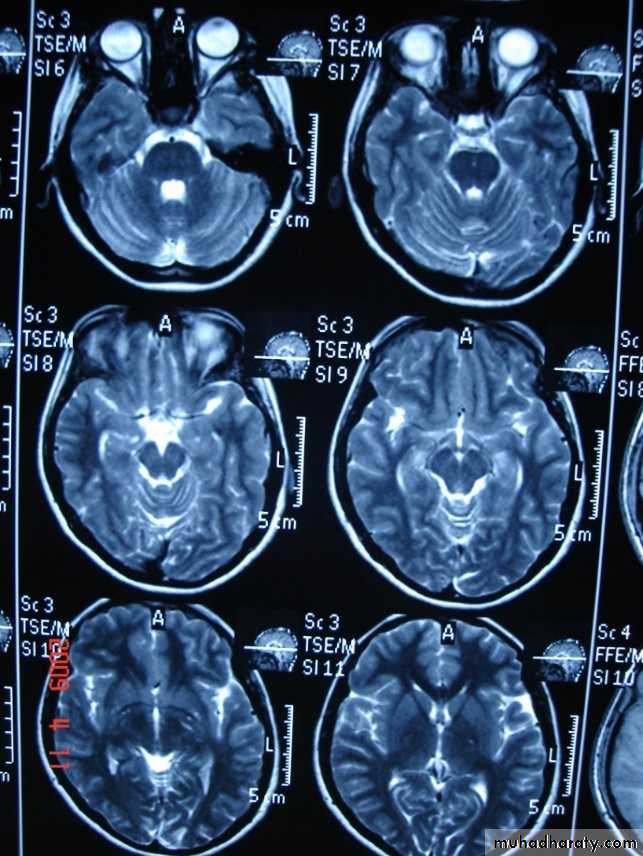

-MRI is more sensitive than CT in the demonstration of MS plaques.

- the most characteristic appearance is that of peri ventricular nodular Hyper intense lesions on T2 weighted images.

-the plaques are also well seen at the gray- white matter interfaces.

-MRI can even image lesions in the spinal cord , brainstem & cerebellum.

-multiple cerebral lesions are seen in over half the patient presenting with a single episode of optic neuritis.

-some lesion may show a central area of greater signal intensity , resembling a target.

-contrast enhancement after giving gadolinium occurs in the acute phase indicating activity & in the chronic phase doesn't enhance.

MRI